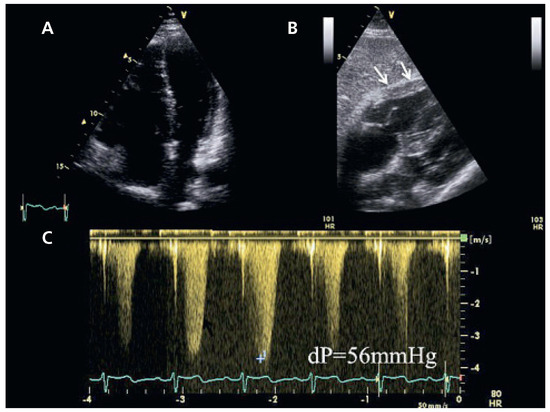

Une échocardiographie transthoracique est donc demandée à la recherche d’une étiologie cardiaque à la dyspnée. Cet examen montre une fonction systolique biventriculaire conservée, une hypertrophie importante et une dilatation modérée du ventricule droit (Figure 1). La pression systolique dans l’artère pulmonaire, calculée au moyen de la vitesse maximale de régurgitation tricuspidienne est estimée à 65 mm Hg. La recherche soigneuse d’un shunt G/D ne met pas en évidence de défect du septum interauriculaire.

Figure 1. (A) Vue en 4 cavités en diastole. Dilatation des cavités droites. (B) Vue sous-costale en diastole: hypertrophie de la paroi libre du ventricule droit (flèches). (C) Flux de régurgitation tricuspidien permettant d’évaluer la pression systolique pulmonaire à 65 mm Hg en estimant la pression de l’oreillette droite à 10 mm Hg.